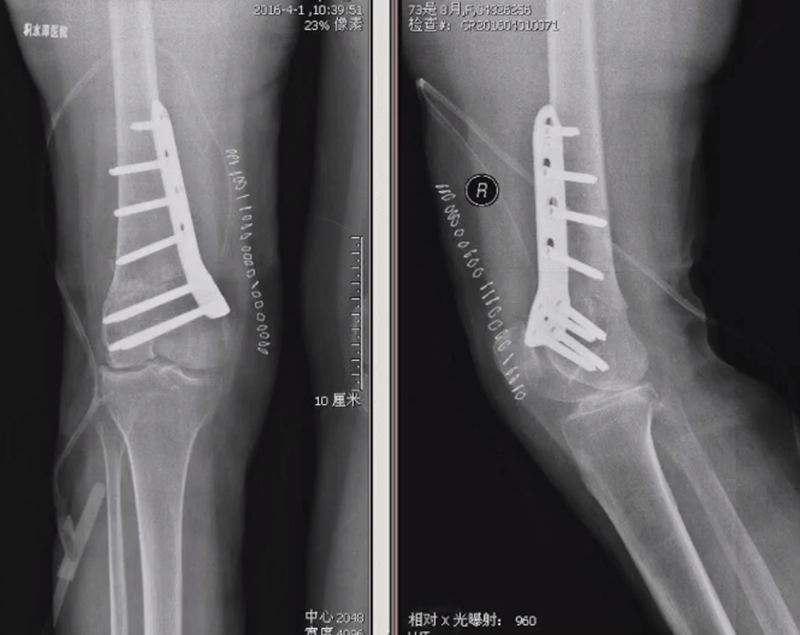

病例,X患者,女,双侧外翻膝,行双侧DFO。

术后6周摔伤,一侧出现膝内翻。

影像学检查显示左侧出现合页断裂。

进行翻修,术前力线显示内翻。